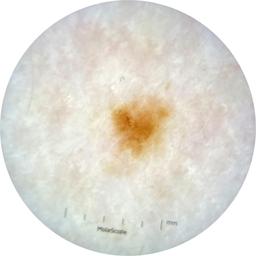

ISIC_9785574

image_type dermoscopic

lesion_id IL_0236417